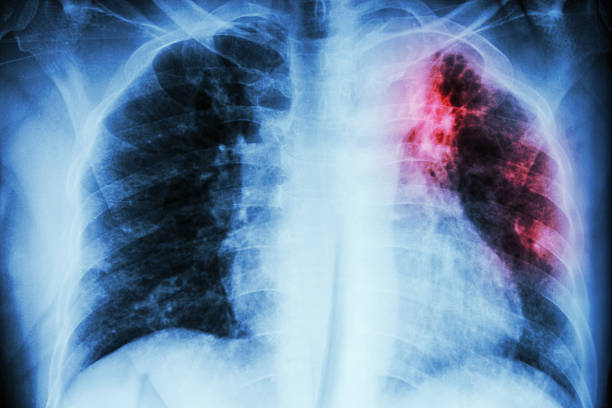

CANAL SAÚDE Tuberculose: 70 mil brasileiros são diagnosticados por ano

O Brasil está entre os países com mais casos da doença. De acordo com o Ministério da Saúde, por ano, 70 mil brasileiros são diagnosticados com tuberculose. Hoje, 24 de março, é o Dia Mundial de Combate à Tuberculose. Para falar sobre o assunto, Jota Batista conversou, no Canal Saúde desta sexta-feira (24), com o cirurgião torácico Rafael Tavares.

De acordo com o médico, a tuberculose se torna um problema maior quando acomete crianças, idosos e imunocomprometidos.

Ela está muito associada à imunodeficiência, então, nos extremos de idade, costuma ser um problema maior. Vale salientar que toda criancinha, no Brasil, quando nasce, precisa tomar uma vacina, que é a BCG, para evitar os casos extremamente graves que acontecem em recém-nascidos”, explicou.

O tratamento da tuberculose, segundo o profissional de saúde, é longo, porém muito eficaz.

É medicamentoso, com antibióticos. Tem que tomar os remédios todos os dias durante seis meses, normalmente, para a tuberculose pulmonar. É um acompanhamento que na rede SUS é entregue de forma gratuita”, disse o cirurgião.